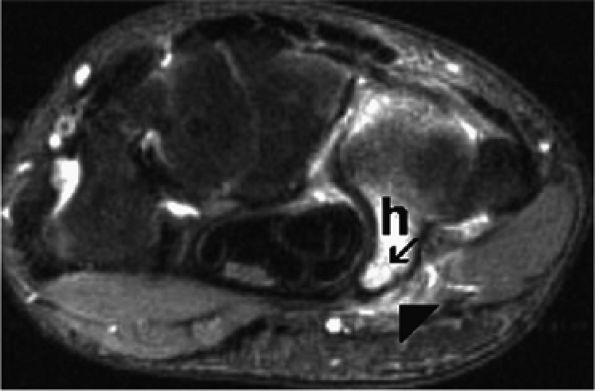

FIGURE 12.47 ● Ulnar neuropathy secondary to fracture of the hook of the hamate. Axial fat-suppressed T2-weighted image demonstrates a non-displaced fracture (arrow) of the hook of the hamate (h) associated with edema within Guyon's canal (arrowhead).